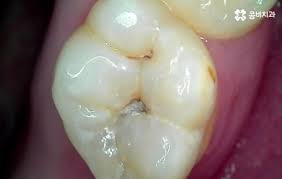

신경치료 후 치아는 내부 구조가 약해져 쉽게 깨질 수 있습니다. 크라운은 이를 보호하고, 씹는 기능과 심미성을 복원해주는 중요한 치료 단계로, 선택이 아닌 필수입니다.

크라운은 손상된 치아 위를 씌우는 인공 보철물로, 치아를 외부 충격에서 보호하고 정상 기능과 자연 외형을 회복시켜 줍니다. 어금니는 내구성, 앞니는 심미성을 고려해 재료를 선택하는 것이 핵심입니다.